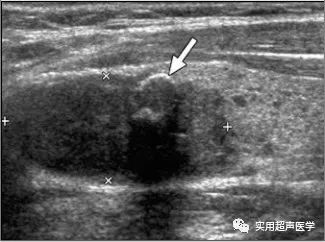

患者,女,55岁,桥本甲状腺炎合并乳头状癌(FNA)。甲状腺左侧叶纵切可见实性低回声结节(光标)与内部钙化(箭头)。